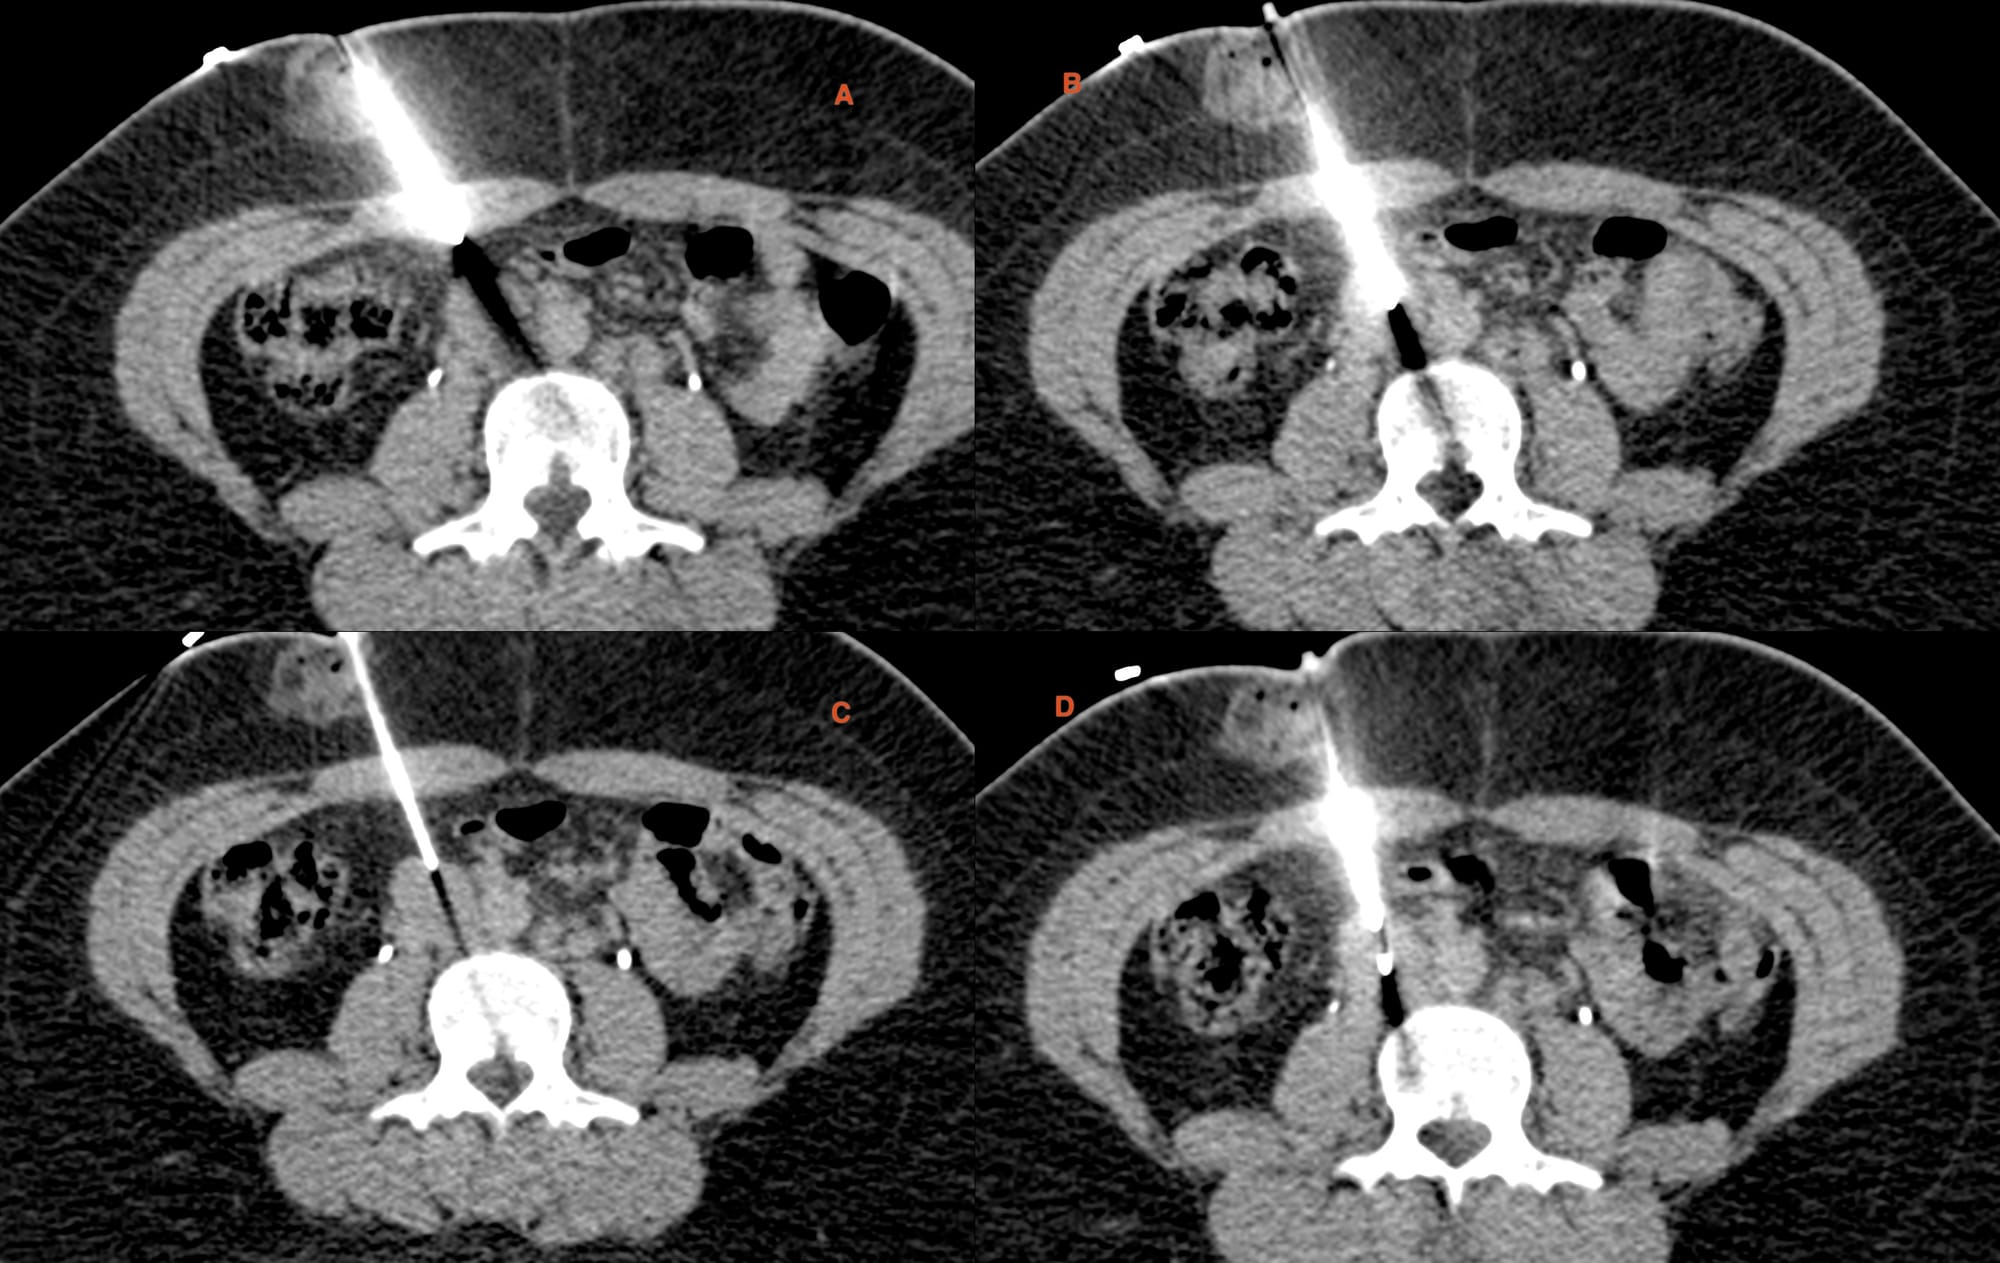

Fig. 4. Panel shows the 18G BARD, 20 mm throw gun with a straight entry into the node (A, B). After withdrawing the stylet, the canal is pulled up to the proximal edge of the node (C). I used a hub to reduce the throw to 10 mm (D) and deployed the gun.